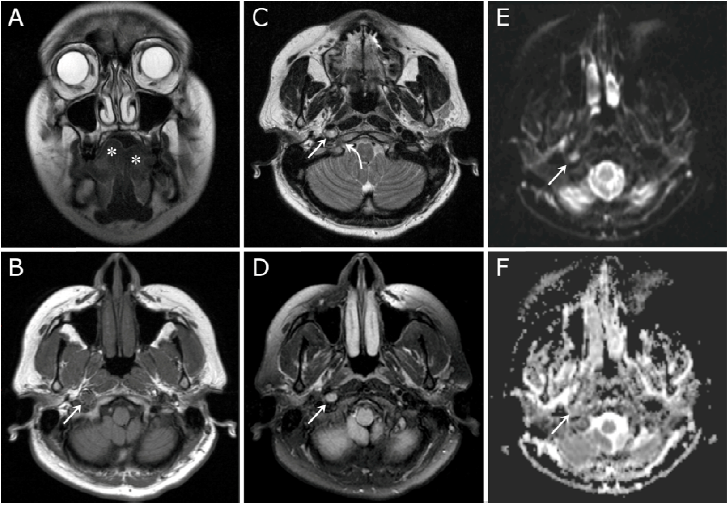

A 33-year-old female presented with deviation of her tongue towards the right side (Figure 1, A). Magnetic resonance imaging (MRI) of the head revealed a 1.0 x 0.8cm mass abutting the right internal carotid artery in close proximity to the hypoglossal canal. The mass proved relatively isointense to brain parenchyma on T1 weighted images (Figure 1, B), slightly hyperintense on T2 weighted images (Figure 1, C), with a higher signal intensity on T2-tirm imaging (Figure 1, D). A “T2 shine through” phenomenon was also noted on Diffusion Weighted Imaging (DWI) with Apparent Diffusion Coefficient (ADC) mapping (Figure 1, E and F), the findings being consistent with a hypoglossal neurinoma (schwannoma) of the carotid space segment.